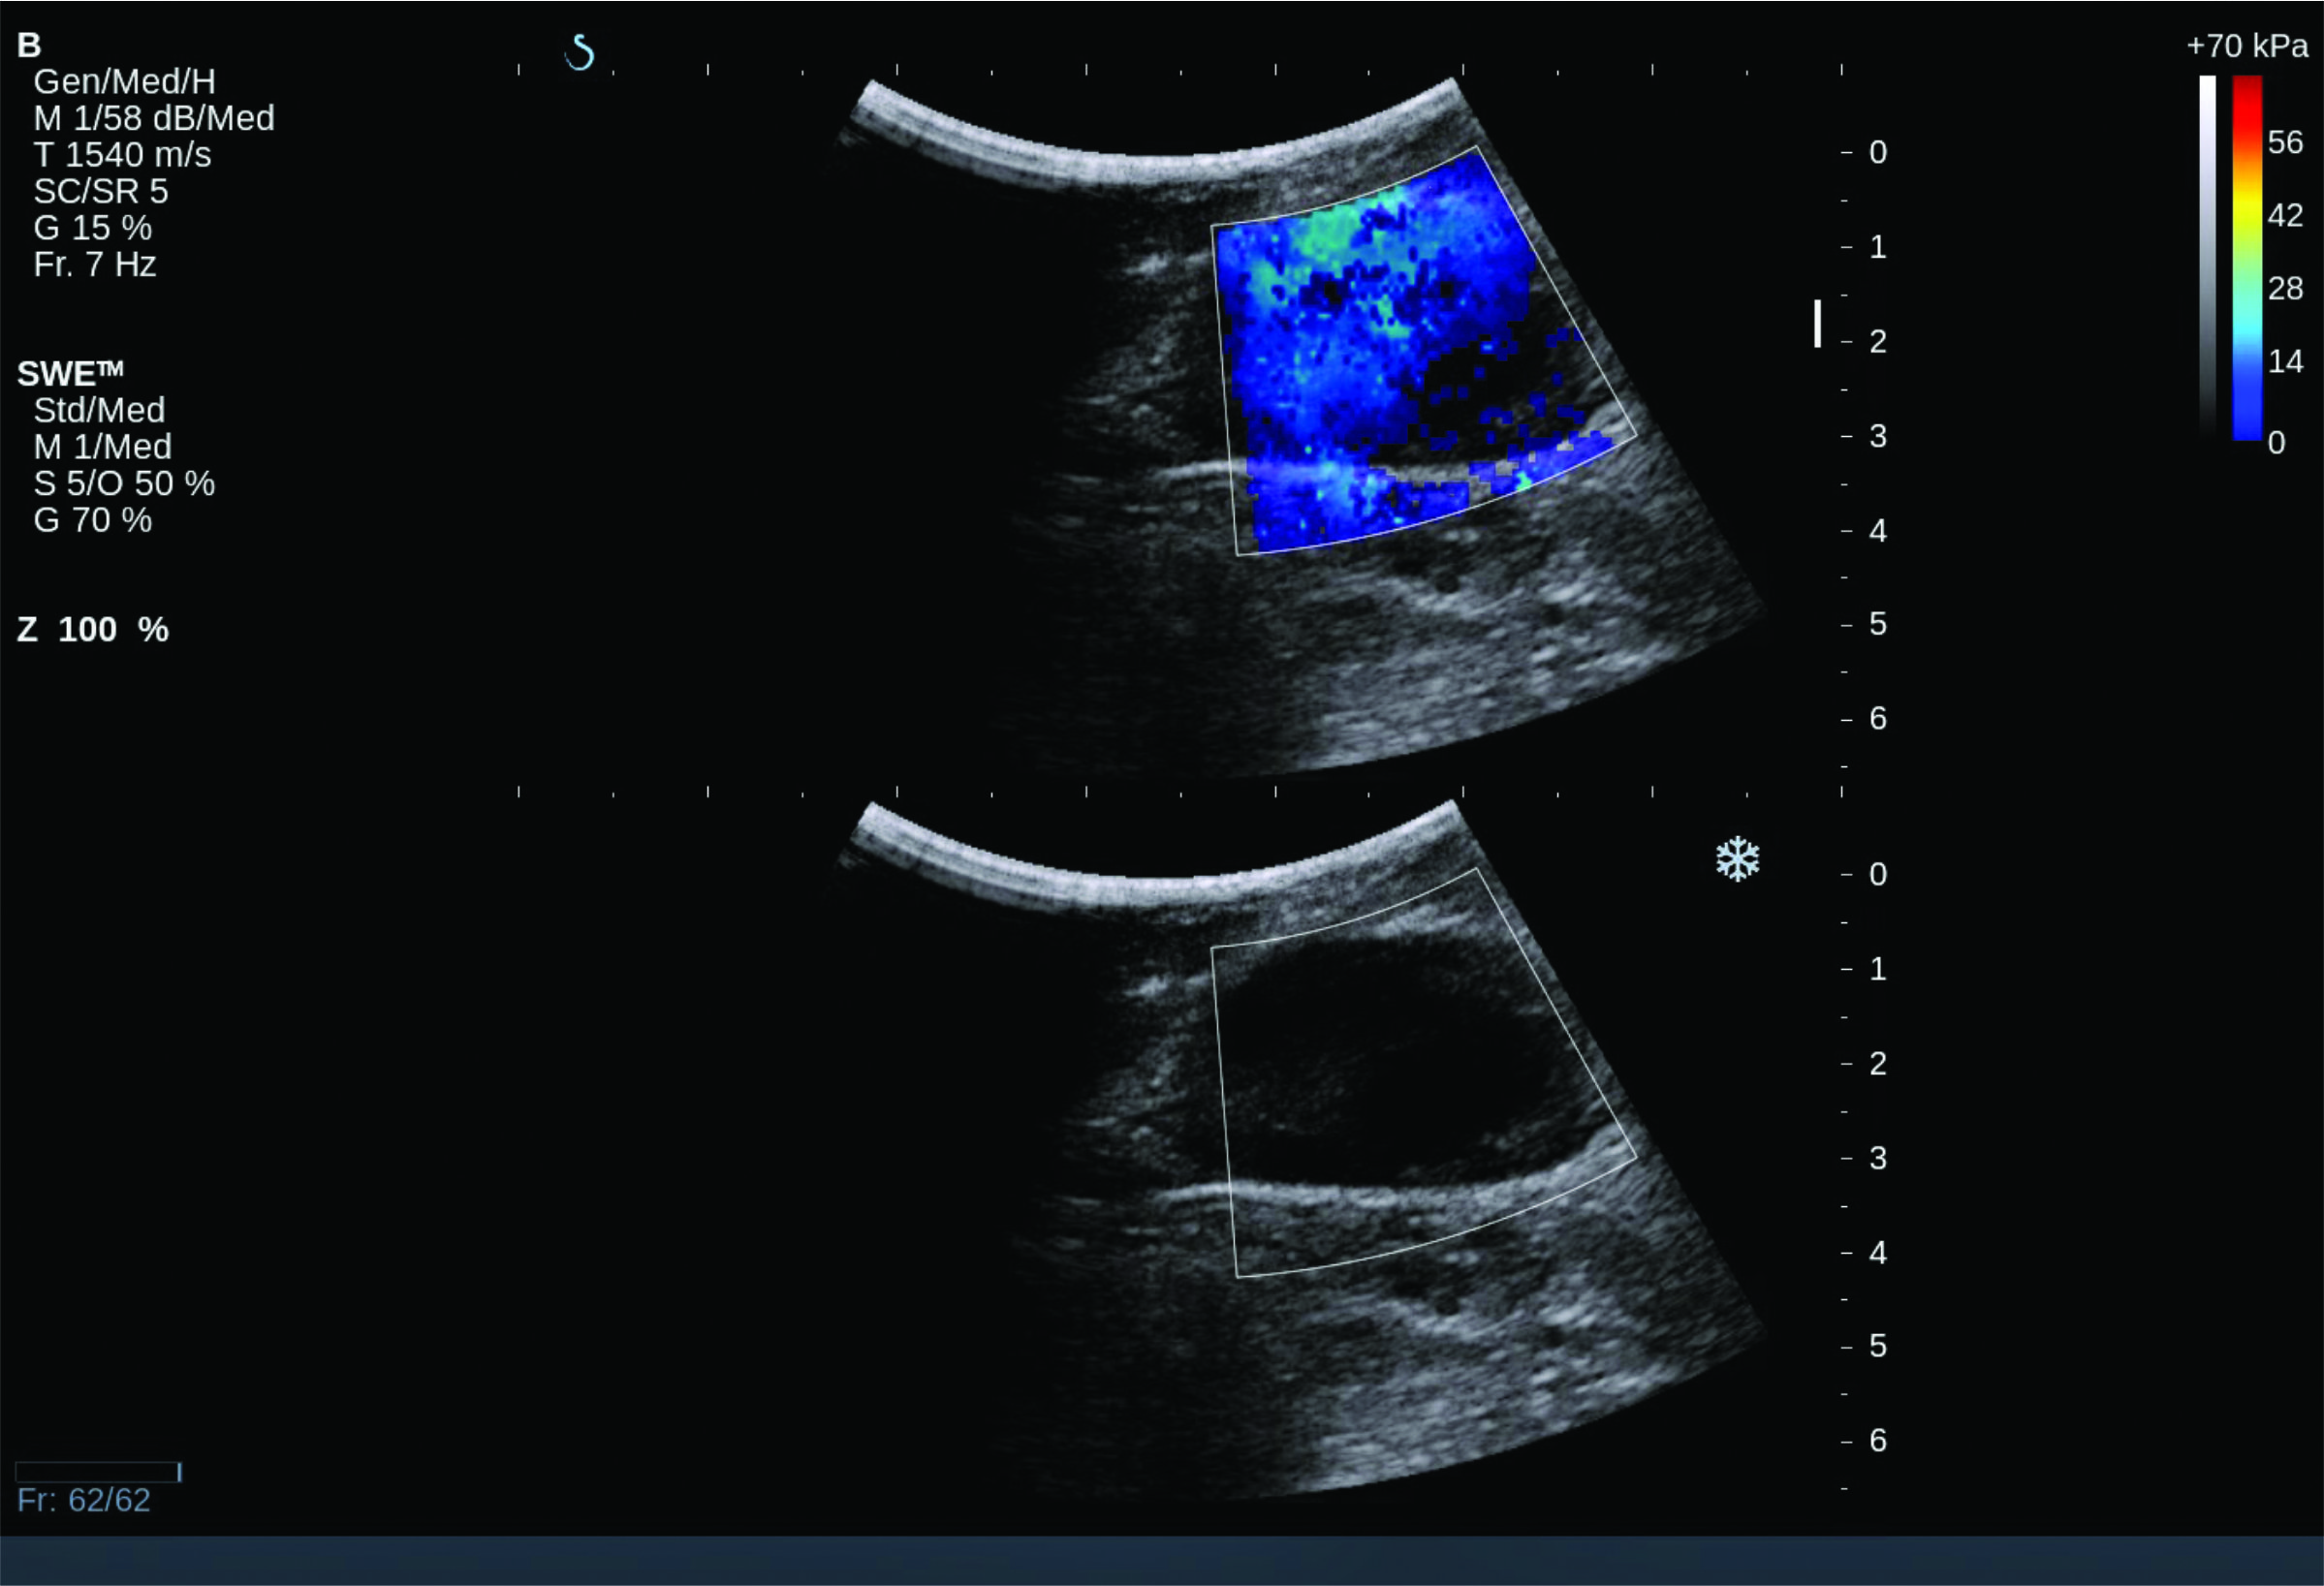

Fig 2 shows B-mode and CF images on the top and side and CW velocity peak detection on the bottom. This is an image taken from a patient with a bad heart valve. The negative cusps on the bottom image indicate the presence of a condition called tricuspid regurgitation.